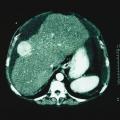

Kyste hépatique simple (ou biliaire)

TUMEURS DU FOIE

ECHINOCOCCOSE HEPATIQUE